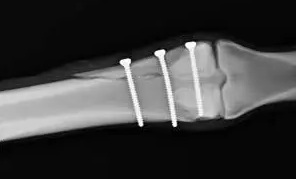

ラグスクリューまたは骨片間スクリュー

ラグスクリューまたは骨片間スクリューは、特定の骨折、特に長い斜骨折に対して選択肢となります。原則として、骨折長が骨幅の2.5倍を超える場合は、ラグスクリューの使用を検討できます。この固定法はKワイヤーよりも安定性が高く、プレートやスクリューの設置に伴う軟部組織の剥離を必要としません。